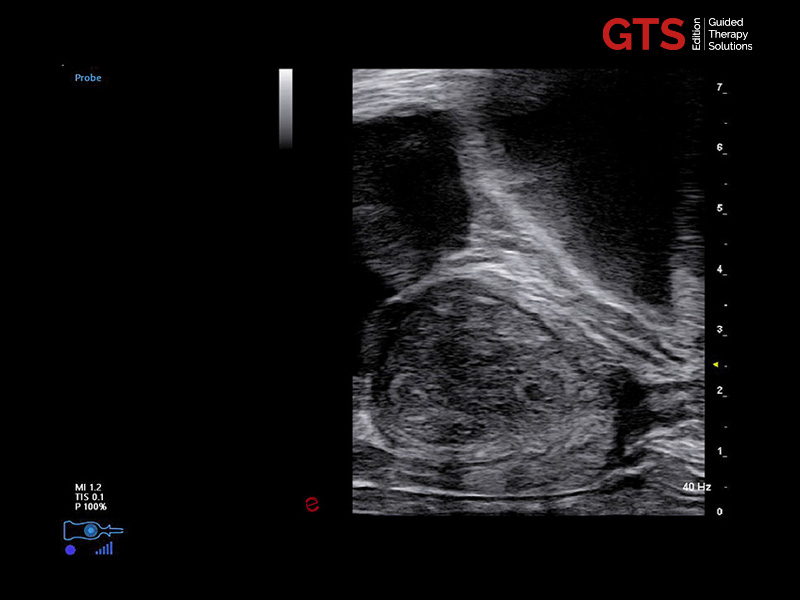

Prostate in axial view using E 3-12 - End-fire probe, E 3-12

Prostate in sagittal view using TLC 3-13 - Bi-planar probe, TLC 3-13